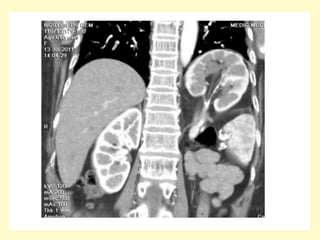

Ectopic pelvic kidney, Volume rendering (a) demonstrates absence of the left

kidney at the left renal fossa, instead, an ectopic left pelvic kidney is seen,

the axial contrast-enhanced MDCT image (b) shows an engorged left iliac

vein (asterisk), due to left aberrant renal vein (not shown), the ectopic

kidney receives blood supply from two renal arteries arising form the aorta

(arrowhead) and left iliac artery (arrow)

• 7.

Ectopic pelvic kidney,Volume rendering (a) demonstrates absence of the left kidney at the left renal fossa, instead, an ectopic left pelvic kidney is seen, the axial contrast-enhanced MDCT image (b) shows an engorged left iliac vein (asterisk), due to left aberrant renal vein (not shown), the ectopic kidney receives blood supply from two renal arteries arising form the aorta (arrowhead) and left iliac artery (arrow)